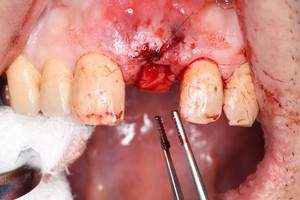

インプラント治療の症例1

レントゲン写真

- 透過像

症例写真-1

- Befor

- After

症例写真-2

- 途中経過

| 年齢 | 50代・男性 |

|---|---|

| 主訴 | 右下歯が疼く |

| 治療内容 | ・右下6番インプラント ※1:FGG(遊離歯肉移植術)とは、足りない歯ぐきを上顎から上皮を切り取り移植する外科手術 |

| 治療費 | 合計:902,000円(税込) ■内訳 |

| 治療期間 | 9ヵ月 |

| 治療方針 | 右下の当該歯は歯根破折により保存不可能と診断しました。歯周疾患も伴っていたため抜歯後に骨吸収※1が大きく起こることが予測できました。チタンメッシュ併用骨再生誘導法(GBR※2)を選択しインプラント埋入と同時に行い自然な歯槽骨のラインを再現しました。またGBRを行う際にインプラント辺縁の付着歯肉の減少が起こる為、遊離歯肉移植術(FGG※3)を行い清掃性を考慮した形態に仕上げました。 ■治療方針の解説 治療した右下の歯をレントゲンで撮影したところ根本の部分に黒く写る箇所があり「根尖性慢性周囲炎※1」と診断。また歯周病も進行していました。 ※1 骨吸収・・・歯槽骨という歯を支える骨がなくなっていくこと |

| 担当者所見 | 主訴の右下だけでなく歯茎の腫れ、発赤があり不良補綴や不良充填など他にも治療箇所が多数ありました。プラークコントロールが不良であった為まずはブラッシング指導を行いセルフケアの重要性を理解していただくところからスタートしました。 右下6番の歯はインプラント治療を行なった結果審美的にも機能的にも患者様の満足を得ることができました。骨造成と歯肉移植も行なった為インプラントを支える十分な歯周組織の獲得ができたと思っております。 |